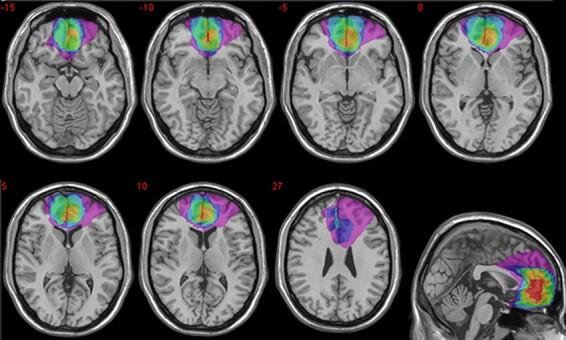

Self-related information is remembered better than other-related information (self-reference effect; SRE), a phenomenon that has been convincingly linked to the medial prefrontal cortex. It is not clear whether information related to our future self would also have a privileged status in memory, as medial prefrontal cortex (mPFC) regions respond less to the future than to the present self, as if it were an 'other'. Here we ask whether the integrity of the ventral mPFC (vmPFC) is necessary for the emergence of the present and future SRE, if any. vmPFC patients and brain-damaged and healthy controls judged whether each of a series of trait adjectives was descriptive of their present self, future self, another person and that person in the future and later recognized studied traits among distractors. Information relevant to the present (vs future) was generally recognized better, across groups. However, whereas healthy and brain-damaged controls exhibited strong present and future SREs, these were absent in vmPFC patients, who concomitantly showed reduced certainty about their own present and anticipated traits compared to the control groups. These findings indicate that vmPFC is necessary to impart a special mnemonic status to self-related information, including our envisioned future self, possibly by instantiating the self-schema.

自我相关的信息比他人相关的信息更容易被记住(自我参照效应;SRE),这一现象已经被令人信服地与内侧前额叶皮层联系起来。目前尚不清楚与我们未来的自我相关的信息在记忆中是否也具有特殊地位,因为内侧前额叶皮层(mPFC)区域对未来的自我反应不如对现在的自我反应强烈,就好像它是“他人”一样。在这里,我们想知道腹内侧前额叶皮层(vmPFC)的完整性是否是出现现在和未来 SRE 的必要条件,如果有 SRE 的话。vmPFC 患者和脑损伤患者以及健康对照组判断一系列特质形容词中哪些形容词描述了他们现在的自我、未来的自我、另一个人和未来的那个人,之后在干扰项中识别出学习过的特质。信息与现在(而不是未来)相关的信息通常更容易被识别,这在所有组中都是如此。然而,健康对照组和脑损伤对照组表现出强烈的现在和未来 SRE,而 vmPFC 患者则没有表现出这种 SRE,同时与对照组相比,他们对自己现在和预期的特质的确定性也降低了。这些发现表明,vmPFC 是将特殊的记忆状态赋予自我相关信息所必需的,包括我们设想的未来自我,可能是通过实例化自我图式来实现的。